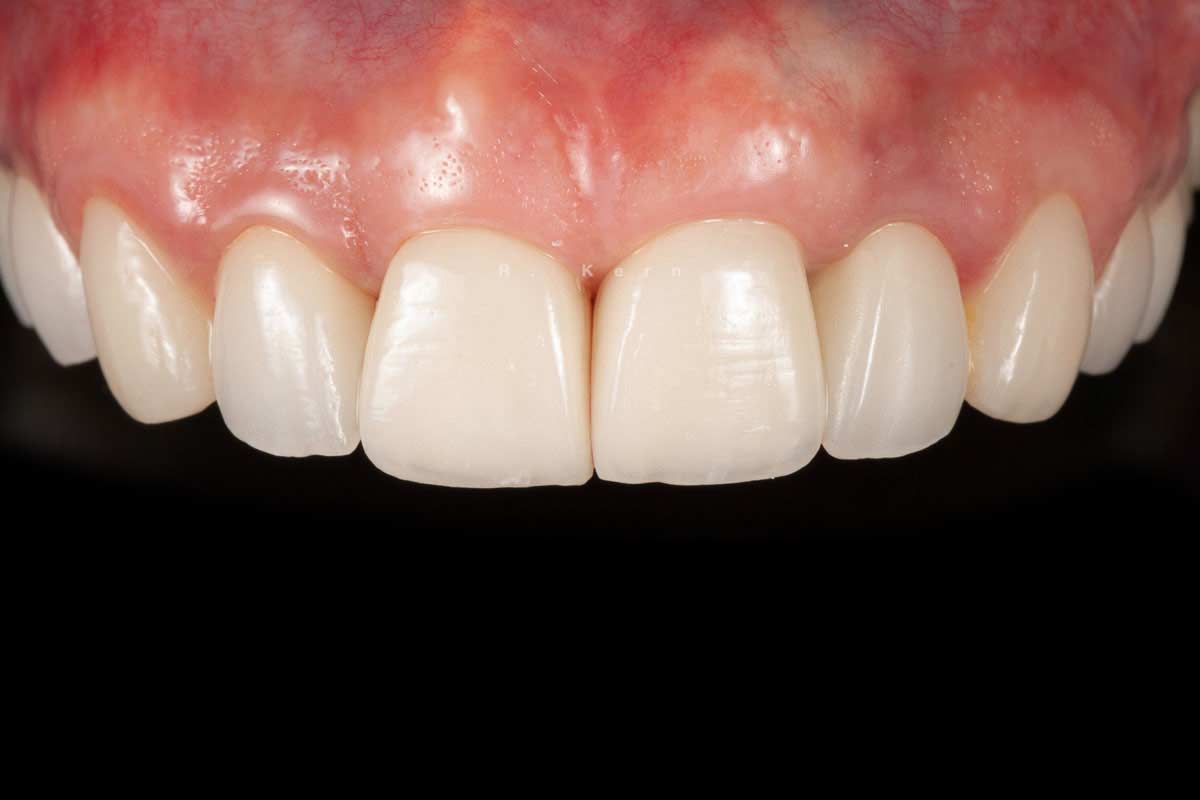

11/12 - Final restoration

Immediate implant placement and periimplant bone augmentation using cerabone® - Dr. R. Kern